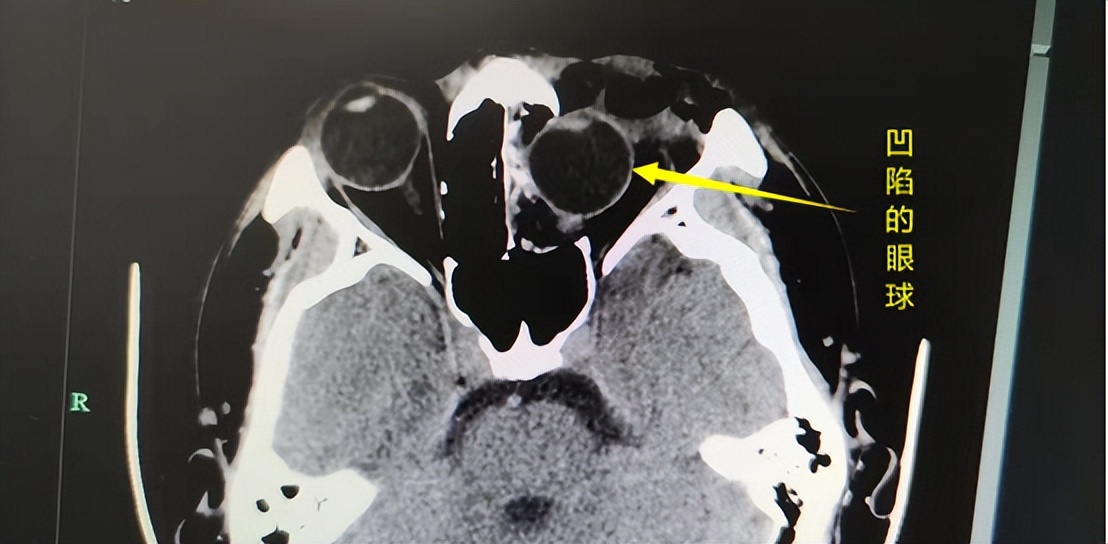

张某眼球明显内陷

救护车赶到后第一时间将他送到我院急诊。接诊的急诊外科主治医师谢杰马上对张某进行检查。检查发现,虽然伤情在外观上看着并不重,但张某左眼已经完全失明,左眼眼眶骨折,眼球凹陷明显,并且内陷达到1厘米,整个眼球的一半已经嵌到鼻腔里面。

伤情严重,谢杰马上呼叫眼科会诊,眼科值班医生张春明马上赶来,对张某进行进一步检查。尽管从CT影像上张某眼球外形完整,但受到外力撞击,眼球破裂的可能性不小,视神经也可能受到损伤。并且这些伤情都必须在手术中才能得到明确,后续治疗也才能明确和跟进。并且张某的伤情严重,根本拖不起,耽搁得越久,视力恢复的希望就越渺茫。